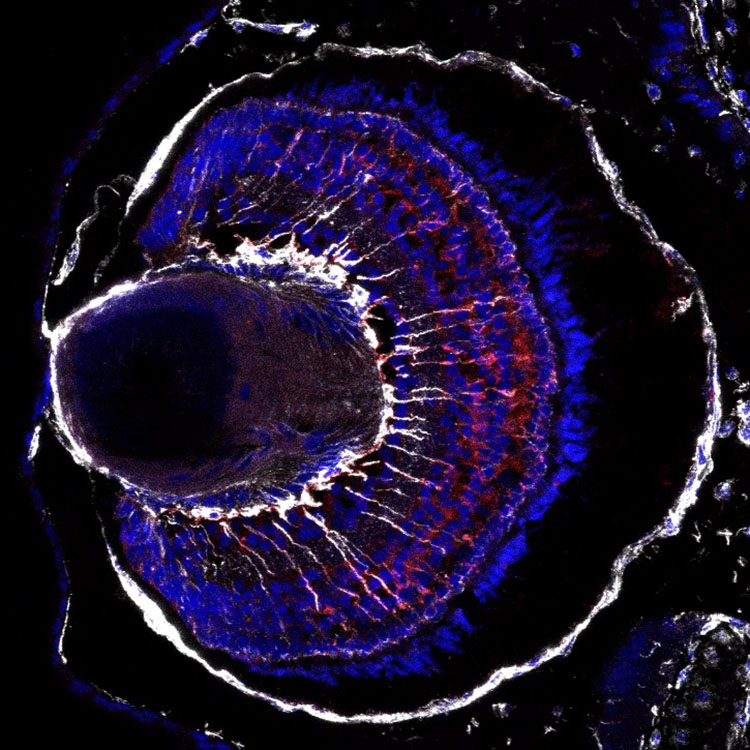

Tissue engineering and regenerative ophthalmology is a field that has been making remarkable strides in recent years, revolutionizing the way we treat eye diseases and injuries. Using cutting-edge technologies and innovative approaches, researchers in this field are developing advanced materials, biocompatible scaffolds, and bioactive molecules that can help restore vision and repair damaged eye tissues. From corneal transplants and retinal implants to stem cell therapies and gene editing, the possibilities in tissue engineering and regenerative ophthalmology are truly awe-inspiring. With its potential to improve the quality of life for millions of people worldwide, it's no wonder that this field is considered one of the coolest and most exciting areas of research today.

Stem Cell Derived Retinal Organoids

Endogenous Regeneration